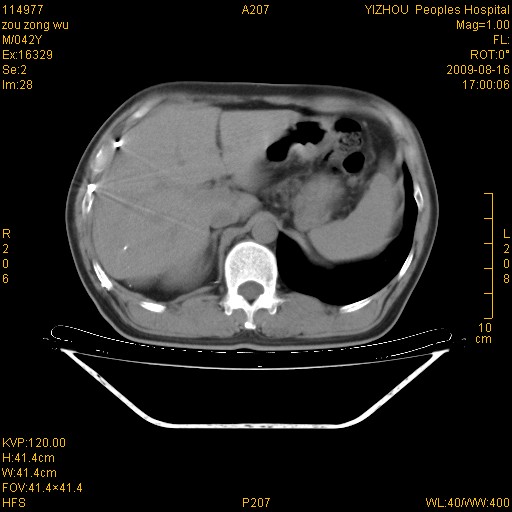

以下是引用zjzjr在2009-8-17 10:42:00的发言:[br]右侧间质性肺炎伴纤维化,右肺下叶肺囊肿伴感染(不除外外伤后引起),右肺野及胸壁软组织\\肝内见多发斑点状,中枪了吧.右侧胸膜肥厚\\粘连.